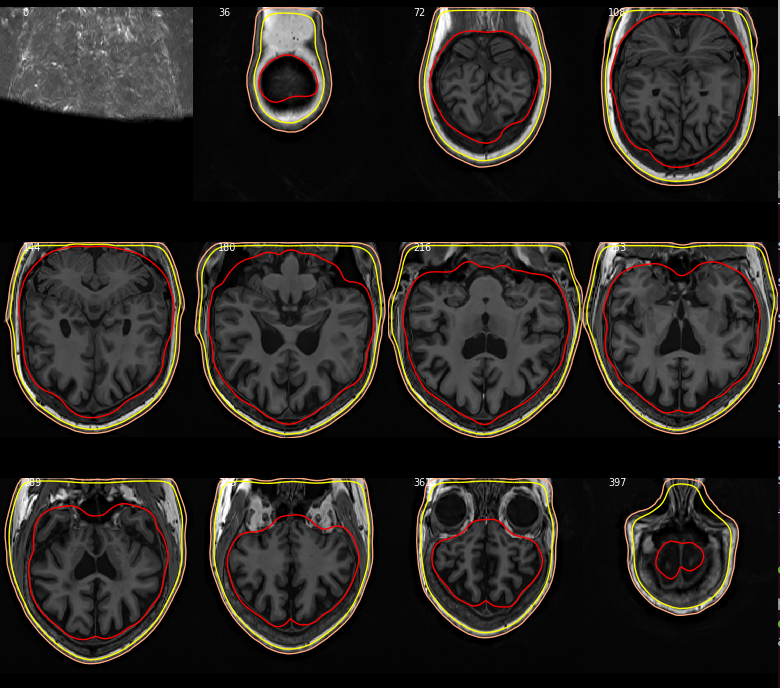

@larsoner Sorry for the late feedback. I do not have the MRI that prompted me to submit the issue #7221 anymore because I went around the issue by preprocessing all my MRI to a "conform" space in the meantime. But I always end up having to move data between pipelines and almost always run into issues with incompatible coordinate systems. So I found some MRI from a different project (originally processed in CIVET rather than FreeSurfer) that were not preprocessed to a conform to space and that is what I got: So... the fix works to the extent that it puts the MRI in coronal view when it is supposed to put it in this view. I think the rest is more about what level of user-friendliness you want to support (i.e., whether or not you would like to have it 100% aware of coordinate system so that it would invert axes if needed to display it in a standard orientation or leave it to the user to provide their MRI in a given coordinate system). At least, right now, it does the volume along the requested axis. FYI, there appears to be some bug in the management of paths: The call at "In [9]" should works as, according to the docstring, the subjects_dir argument can be left to None, in which case "the path is obtained by using the environment variable SUBJECTS_DIR." This error seems to have been introduced with this fix because it works fine when I revert to the MNE version I had before applying this fix. |